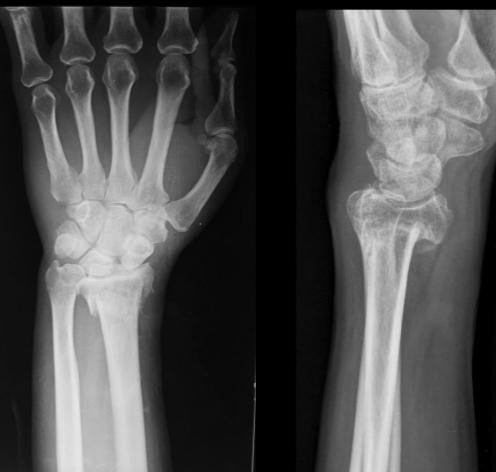

Características Fx colles

A

Mano extendida

Desviación dorsal epifisis

Asociada a osteoporosis >40 años

Características Fx smith

Fx en flexion

Desviación palmar epifisis

Colles

Smith